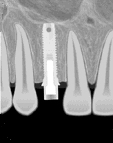

Dental implants are small posts made of biocompatible titanium that act as artificial roots and are the closest substitute to natural teeth in form

and function.